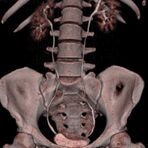

Abdomen (Bauch und Becken)

• Diagnostik von entzündlichen und tumorösen Erkrankungen der Bauchorgane

• Diagnostik von akuten Notfällen wie Darmverschluss, Hohlorganperforation oder Traumafolgen

• Darstellung der großen Gefäße zur Erkennung von Gefäßverschlüssen (z. B. Mesenterial - Arterienembolie oder Einengungen von Gefäßen (z. B. Nierenarterien)

• Darstellung und Therapieplanung von Aneurysmen (CT- Angiographie)

• Virtuelle Kolonographie zur Darstellung des Dickdarmes z. B. bei Kontraindikation zur Darm-Spiegelung oder nur unvollständig durchführbarer Koloskopie.

Wirbelsäule

• Darstellung von Frakturen, Tumoren und Bandscheibenveränderungen

Extremitäten

• bei komplizierten Frakturen z. B. in der Nähe von Gelenken oder im Bereich der Handwurzel und Fußwurzel